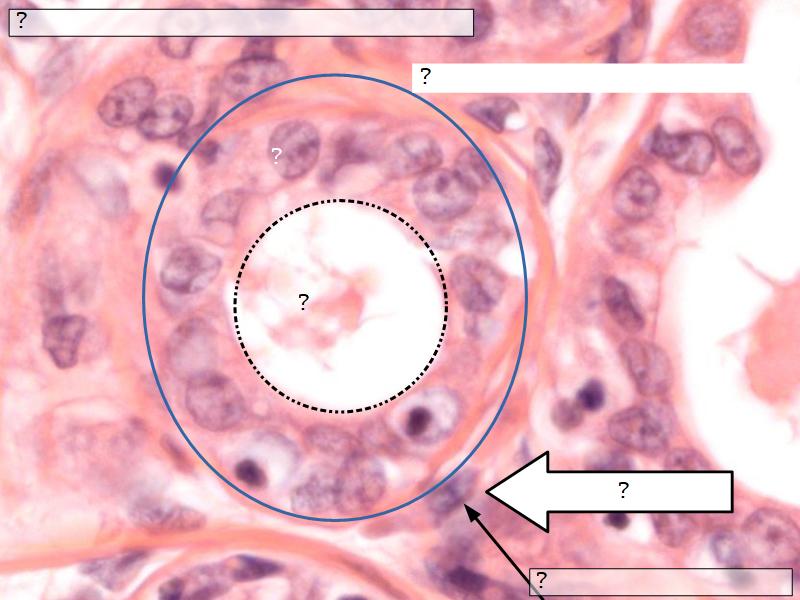

Mammary gland

Write short notes describing the structure of the mammary gland.

(5)

Mammary gland

- Compound tubuloalveolar gland

- 12 - 20 glands

- Each with own lactiferous duct

- Each with own lactiferous sinus

- Opens on skin at apex of nipple

Two stages

- Resting

- Active

Structures

List the structures and cells found in the mammary gland.

Structures

- Lactiferous sinuses

- Stratified squamous near opening on skin

- Stratified cuboidal other parts

- Lactiferous ducts

- Stratified cuboidal

- Myoepithelial cells

- Underlie lactiferous ducts in most areas

- Basal lamina

- Separate epithelial components from stroma

Active gland

- Much larger than resting phase

- Terminal ducts proliferate to form alveoli

- Alveoli

- Surrounded by incomplete myoepithelial cells

Alveolar cells

- Apocrine secretion

- Active state

- Resting state